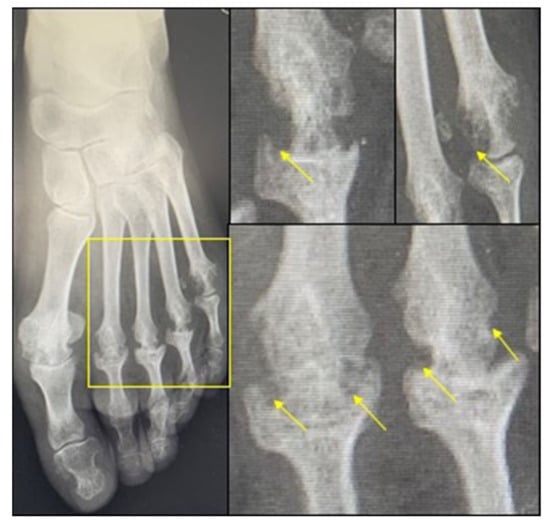

2. Bone Loss in RA

3. Increased Bone Resorption in RA